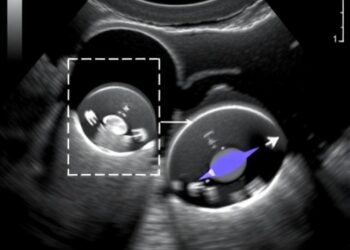

Ultrasound Elastography Advances Fetal Rabbit Lung Assessment

In a remarkable leap forward for prenatal medicine, a groundbreaking study has unveiled a novel, non-invasive technique to evaluate fetal...